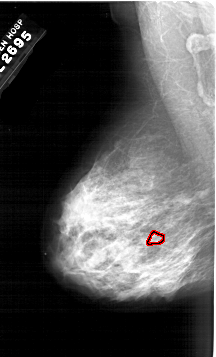

A_1983_1.RIGHT_MLO

RIGHT_MLO LINES 6256 PIXELS_PER_LINE 3796 BITS_PER_PIXEL 12 RESOLUTION 43.5 NON_OVERLAY

ABNORMALITY 1

LESION_TYPE CALCIFICATION TYPE PUNCTATE DISTRIBUTION CLUSTERED

ASSESSMENT 4

SUBTLETY 1

PATHOLOGY MALIGNANT

TOTAL_OUTLINES 1